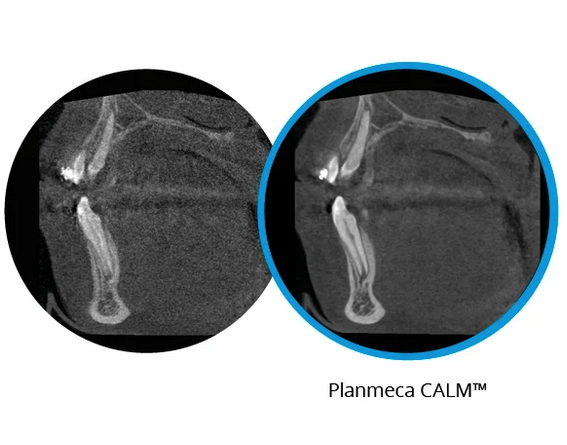

El movimiento de los pacientes es un reto importante para la calidad de la imagen, pero el algoritmo de corrección de movimiento Planmeca CALM® ayuda a eliminar de manera eficaz los artefactos de movimiento de las imágenes CBCT y sale airoso en cada ocasión.